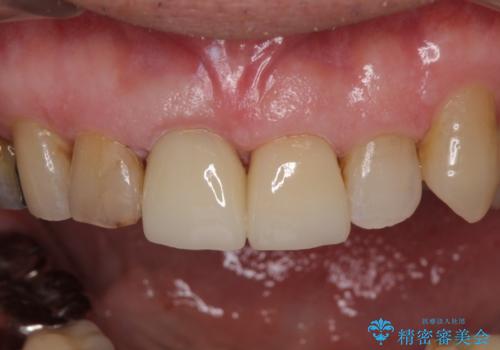

- 前歯がぐらつくことを主訴にご来院された患者様です。ご本人は抜歯と考えており、インプラント以外の治療をご希望でした。しかしながらぐらついていた原因は、古い差し歯が取れかけていたことでした。

遠方から通院されること、仕事上短期間で治療したいとのことを考慮して、残っている歯はかなり小さいものの、保存すべきと判断して当日処置から行いました。

西日本から新幹線でご来院された患者様です。前歯は都内の医院でやりたいとのことで、はるばる通院してくださいました。通院回数が最小限になるよう工夫しました(1回あたりの時間は長くなります)。

残っている歯が小さいと、差し歯はぐらつきやすくなりますが、その形態によっては抜歯を回避できることがあります。